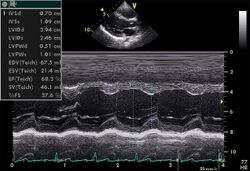

Echocardiogram showing left ventricle

Screening athletes for cardiac disease can be problematic because of low prevalence and inconclusive performance of various tests that have been used. Nevertheless, sudden death among seemingly healthy individuals attracts much public and legislator attention because of its visible and tragic nature.[17]